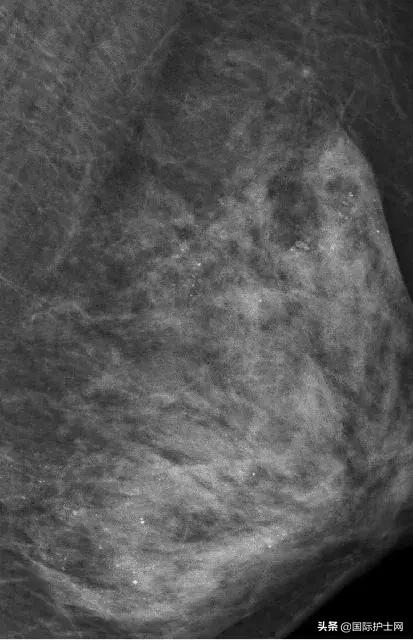

乳房没了,但这场大抢救却依旧在进行。医生在对她的左侧乳房进行乳腺X线检查时,发现里面全部都是细小如沙子一样的钙化灶,布满整个乳腺。

在X光片下,朱女士的乳腺里

满是星星点点的钙化灶